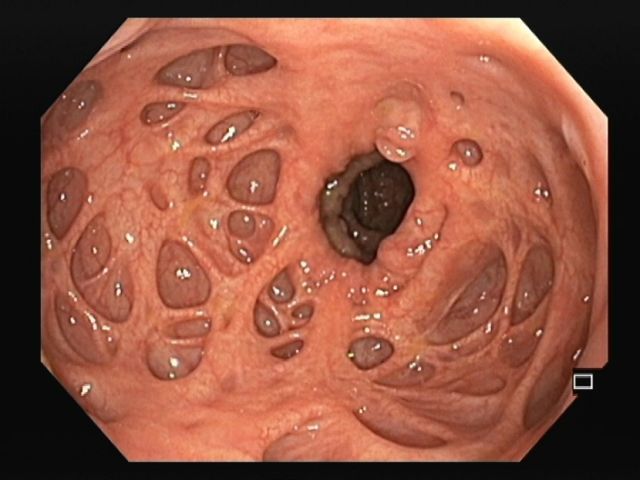

A mantle of rosaries along the colon

2º Prémio - Fotografia